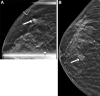

Background Guidelines recommend annual surveillance imaging after diagnosis of ductal carcinoma in situ (DCIS). Guideline adherence has not been characterized in a contemporary cohort. Purpose To identify uptake and determinants of surveillance imaging in women who underwent treatment for DCIS. Materials and Methods A stratified random sample of women who underwent breast-conserving surgery for primary DCIS between 2008 and 2014 was retrospectively selected from 1330 facilities in the United States. Imaging examinations were recorded from date of diagnosis until first distant recurrence, death, loss to follow-up, or end of study (November 2018). Imaging after treatment was categorized into 10 12-month periods starting 6 months after diagnosis. Primary outcome was per-period receipt of asymptomatic surveillance imaging (mammography, MRI, or US). Secondary outcome was diagnosis of ipsilateral invasive breast cancer. Multivariable logistic regression with repeated measures and generalized estimating equations was used to model receipt of imaging. Rates of diagnosis with ipsilateral invasive breast cancer were compared between women who did and those who did not undergo imaging in the 6-18-month period after diagnosis using inverse probability-weighted Kaplan-Meier estimators. Results A total of 12 559 women (median age, 60 years; IQR, 52-69 years) were evaluated. Uptake of surveillance imaging was 75% in the first period and decreased over time (P < .001). Across the first 5 years after treatment, 52% of women participated in consistent annual surveillance. Surveillance was lower in Black (adjusted odds ratio [OR], 0.80; 95% CI: 0.74, 0.88; P < .001) and Hispanic (OR, 0.82; 95% CI: 0.72, 0.94; P = .004) women than in White women. Women who underwent surveillance in the first period had a higher 6-year rate of diagnosis of invasive cancer (1.6%; 95% CI: 1.3, 1.9) than those who did not (1.1%; 95% CI: 0.7, 1.4; difference: 0.5%; 95% CI: 0.1, 1.0; P = .03). Conclusion Half of women did not consistently adhere to imaging surveillance guidelines across the first 5 years after treatment, with racial disparities in adherence rates. © RSNA, 2023 Supplemental material is available for this article. See also the editorial by Rahbar and Dontchos in this issue.

Figures